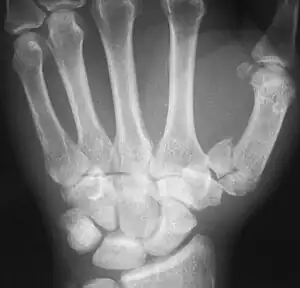

![]() The first metacarpal (Left) | |

Fractures

Fractures to metacarpal bones account for 30-40% of all hand fractures, of which 25% occur in the first metacarpal (second to fractures to the fifth metacarpal bone). 80% of fractures to the first metacarpal occur at its base. [6]

Common fractures to the thumb metacarpal include Bennett's fracture and Rolando's fracture

Fracture of the first metacarpal (Rolando's fracture).